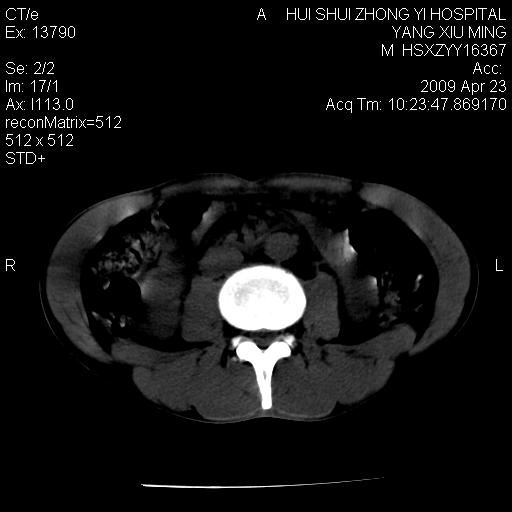

上腹部疼痛一月,呕吐10天,发现左侧颈部包快10天 胸部cr片未见明显异常。

腹膜后淋巴结增大,转移、淋巴瘤?胰腺增大,胰腺炎?占位?颈部考虑增大淋巴结。建议腹部增强扫描。

黑!广泛淋巴结肿大不符合胰腺癌转移。胰腺周围淋巴结肿大致使胰腺看起来大。考虑淋巴瘤可能大。

颈部及腹膜后淋巴瘤可能性大